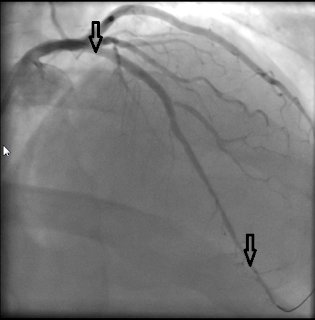

As you can see (or not see) it is missing as it had closed up completely. Dr Husam managed to perform an angioplasty which is to say he inserted two stents which keep the vessel open. After he was finished the same vessel (from a slightly different angle) looks like this

You can clearly see a beautifully open blood vessel between the arrows.